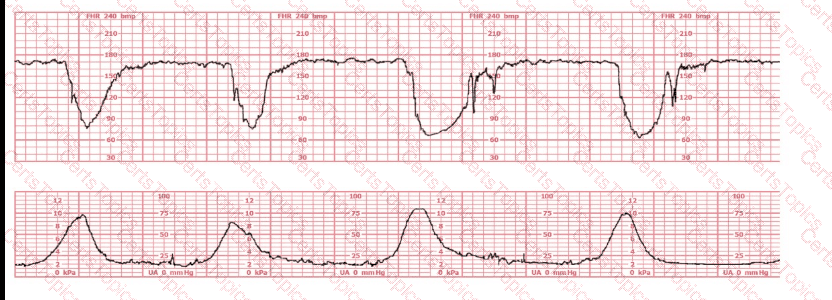

A nulliparous woman at term presents with leaking fluid. Rupture of membranes confirmed. After 6 hours she is completely dilated, +2 station, has been pushing 2 hours with oxytocin at 10 mU/min. The fetal tracing is shown. What is the next step in management?

The decelerations seen in the fetal monitoring tracing shown are best described as:

(Full question)